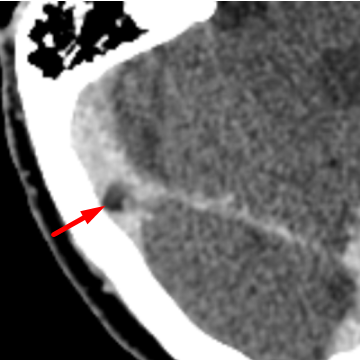

• Small rounded filling defect within the right transverse sinus, compatible with an arachnoid granulation.

• On non-contrast head CT they are CSF density and on post-contrast imaging they appear as round, focal filling defect in the dural sinus.  Usually they are small (<10mm), but occassionally can be “giant” (>10mm).  If they involve the calvarium, they appear as a circumscribed lucent lesion.

• Usually these granulations are easy to differentiate from thrombosis given their round, well-circumscribed appearance and typical location.

Typical appearance of an arachnoid granulation (red arrow).